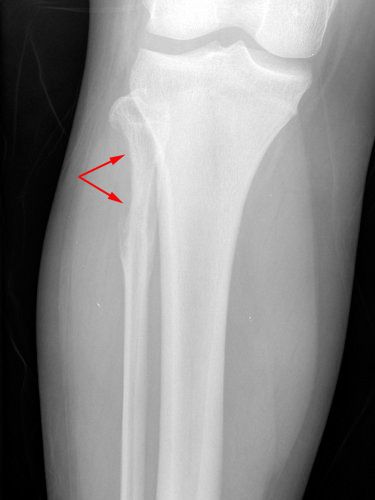

X-ray of knee with Ewing's sarcoma

This X-ray shows the knee of a 14-year-old girl with Ewing sarcoma. The tumor is toward the top of the fibula and has destroyed a portion of the bone.

Reproduced from Domson G, Scarborough M, Gibbs CP: Malignant bone tumors in children. Orthopaedic Knowledge Online 2007. Accessed April 2019.